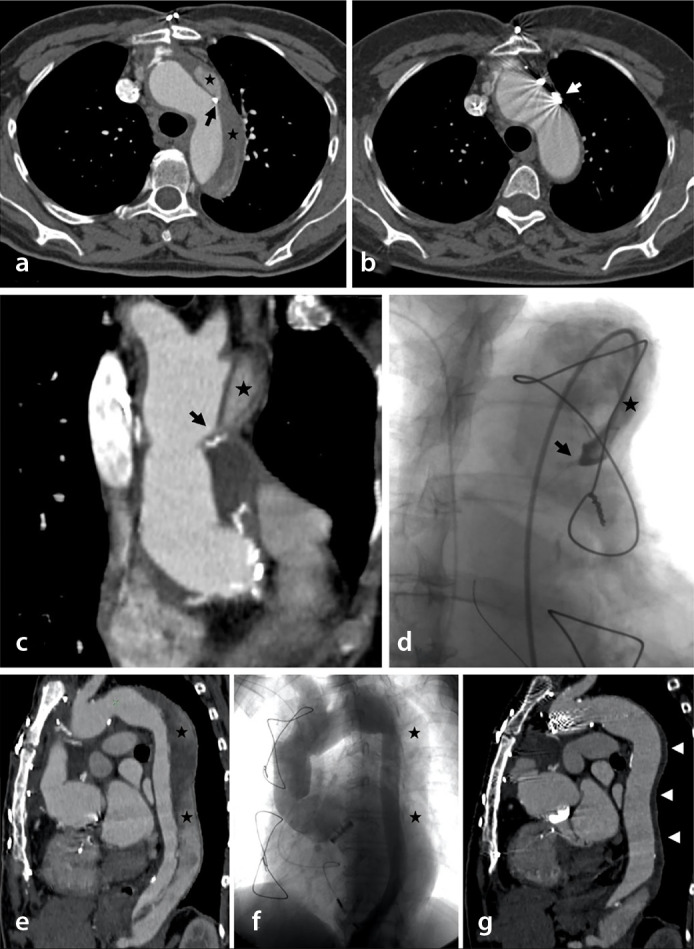

Methods: This retrospective monocentric study included patients treated by CFLO between 2003 and 2022 in the context of chronic AD with progressive descending aneurysmal evolution and persistent circulating false lumen (FL). The procedure was achieved with coils, plugs, and/or glue at the entry tear or in the FL and/or with covered stenting in the supra-aortic trunk. The primary endpoint evaluated the positive aortic remodeling, defined as stabilization or a decrease in the aortic diameter on a computed tomography scan at the 1-year follow-up after the procedure. The FL circulating status, safety, and occurrence of aneurysm events during follow-up were also evaluated.

Abstract Image